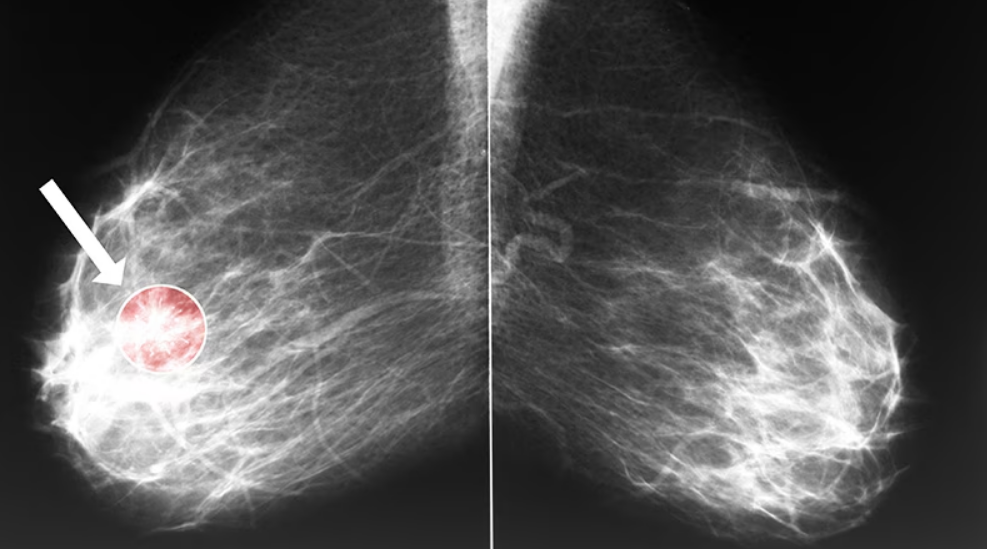

Sur plus de 900 patientes diagnostiquées avant 55 ans (1985-2008), 46 maladies coronariennes ont…